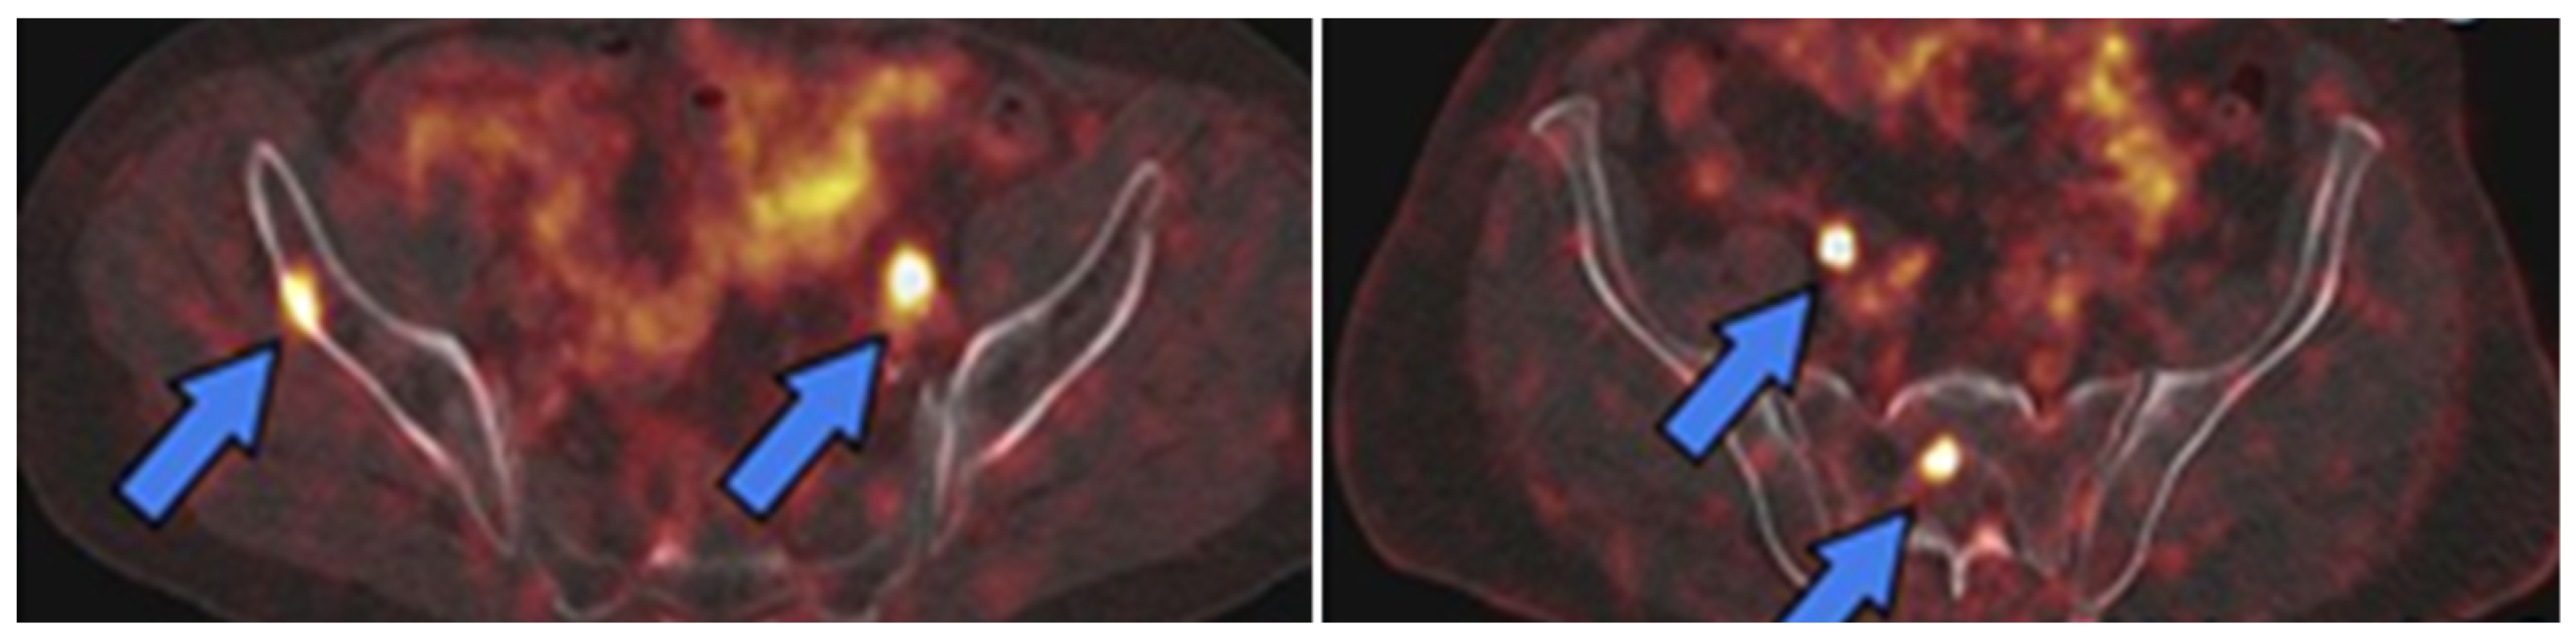

Figure 5. PET tracers approved by the FDA for PSMA-targeted imaging of PCa. (A) [68Ga]Ga-PSMA-11; (B) [18F]DCFPyL.

Figure 6. PET images of PSMA expression in PCa (blue arrows) using [68Ga]Ga-PSMA-11 (left image) and [18F]DCFPyL (right image). This research was originally published in the Journal of Nuclear Medicine (JNM) [61].